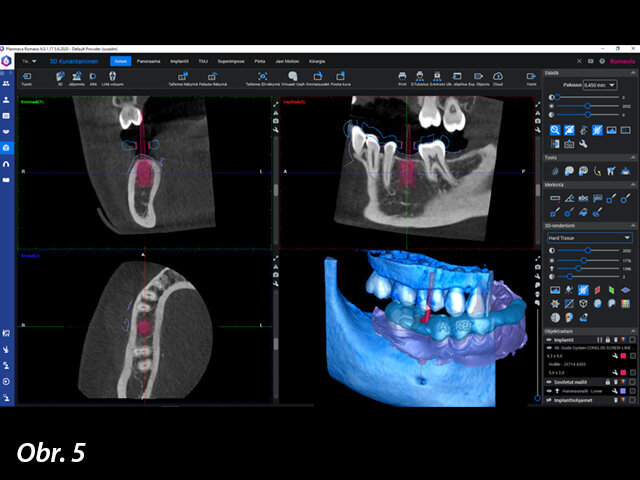

Pro naplánování implantologického ošetření byl nejprve pořízen CBCT snímek pomocí rentgenu Planmeca Viso G7 a zuby byly oskenovány intraorálním skenerem Planmeca Emerald. CBCT snímek a intraorální sken byly zkombinovány v softwaru Planmeca Romexis. Plánování ošetření bylo provedeno v modulu Planmeca Romexis 3D Implant, který obsahuje knihovnu implantátů od více než 100 výrobců. Pro pacientku byl zvolen implantát CONELOG SCREW-LINE od společnosti CAMLOG s průměrem 4,3 mm a délkou 9,0 mm, a jeho zavedení pak bylo pečlivě naplánováno pomocí režimu náhledů na implantát, který je součástí výše uvedeného softwaru.

Plánování implantátu bylo provedeno v softwaru Planmeca Romexis.